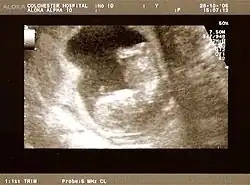

Fetus at 17 weeks

Fetal assessments

Obstetric ultrasonography is routinely used for dating the gestational age of a pregnancy from the size of the fetus, determine the number of fetuses and placentae, evaluate for an ectopic pregnancy and first trimester bleeding, the most accurate dating being in first trimester before the growth of the foetus has been significantly influenced by other factors.[22] Ultrasound is also used for detecting congenital anomalies (or other foetal anomalies) and determining the biophysical profiles (BPP), which are generally easier to detect in the second trimester when the foetal structures are larger and more developed.[23]

X-rays and computerized tomography (CT) are not used, especially in the first trimester, due to the ionizing radiation, which has teratogenic effects on the foetus.[24] No effects of magnetic resonance imaging (MRI) on the foetus have been demonstrated,[25] but this technique is too expensive for routine observation. Instead, obstetric ultrasonography is the imaging method of choice in the first trimester and throughout the pregnancy, because it emits no radiation, is portable, and allows for realtime imaging.[26]

The safety of frequent ultrasound scanning has not been confirmed. Despite this, increasing numbers of women are choosing to have additional scans for no medical purpose, such as gender scans, 3D and 4D scans.[27] A normal gestation would reveal a gestational sac, yolk sac, and fetal pole.[28]

The gestational age can be assessed by evaluating the mean gestational sac diameter (MGD) before week 6, and the crown-rump length after week 6. Multiple gestation is evaluated by the number of placentae and amniotic sacs present.[29]